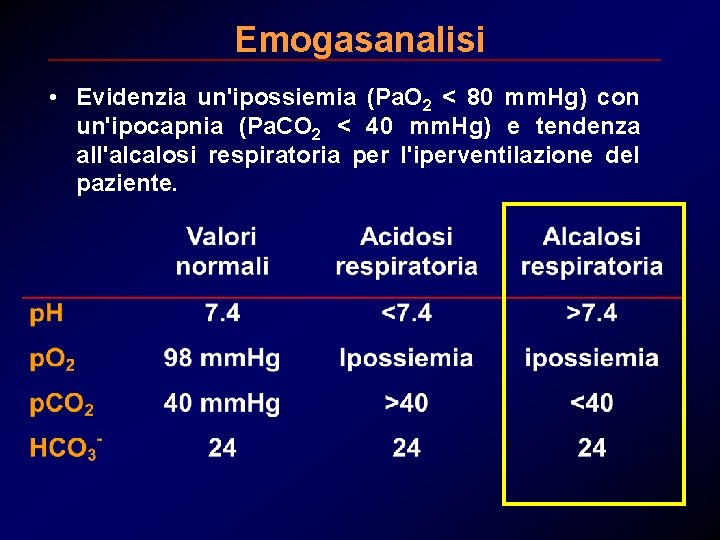

Emogasanalisi • Evidenzia un'ipossiemia (Pa. O 2 < 80 mm. Hg) con un'ipocapnia (Pa. CO 2 < 40 mm. Hg) e tendenza all'alcalosi respiratoria per l'iperventilazione del paziente.